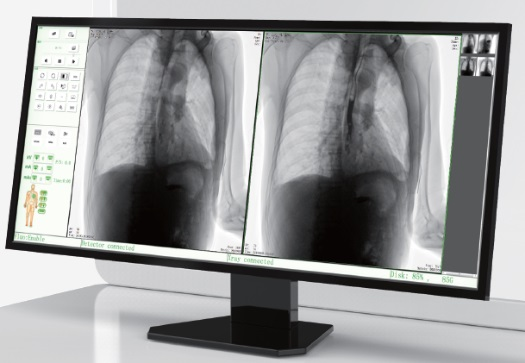

高品質(zhì)影像鏈 讓您看的更清晰 PLX8500C/D

● 無縫對(duì)接醫(yī)院PACS系統(tǒng),幫助實(shí)現(xiàn)信息共享、遠(yuǎn)程診斷。